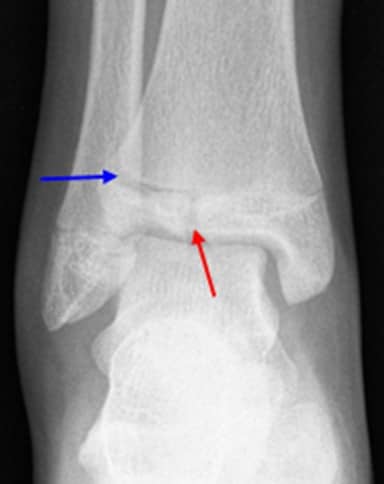

growth plates in ankle

This X-ray of a child's ankle taken from the front clearly shows the growth plates of the tibia and fibula (red arrows).